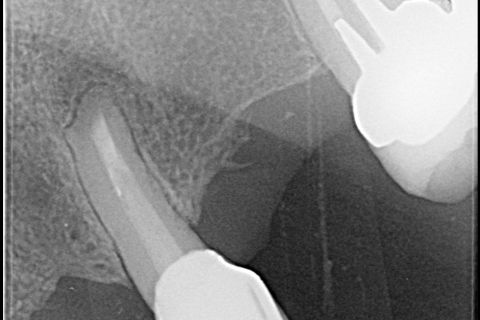

Radiografia inicial

Um paciente do sexo feminino de 68 anos, ASA I, pulso 64 bpm, PS 116 X 68 mmHb, SpO2 98%, Temperatura 36,5oC, chegou ao consultório odontológico queixando-se de dor constante, de baixa intensidade, e espontânea, na área bucal e apical do dente 23 (Figura 1). Ela apresentava um edema intraoral, dor durante a mastigação e percussão vertical. Ela relatou ter sido submetida a um tratamento endodôntico no dente 23 há mais de 35 anos atrás. No exame radiográfico periapical, foi possível visualizar um tratamento endodôntico ineficiente, com uma obturação endodôntica com cone de prata e a presença de periodontite apical sintomática. Foi diagnosticado um abscesso apical agudo.